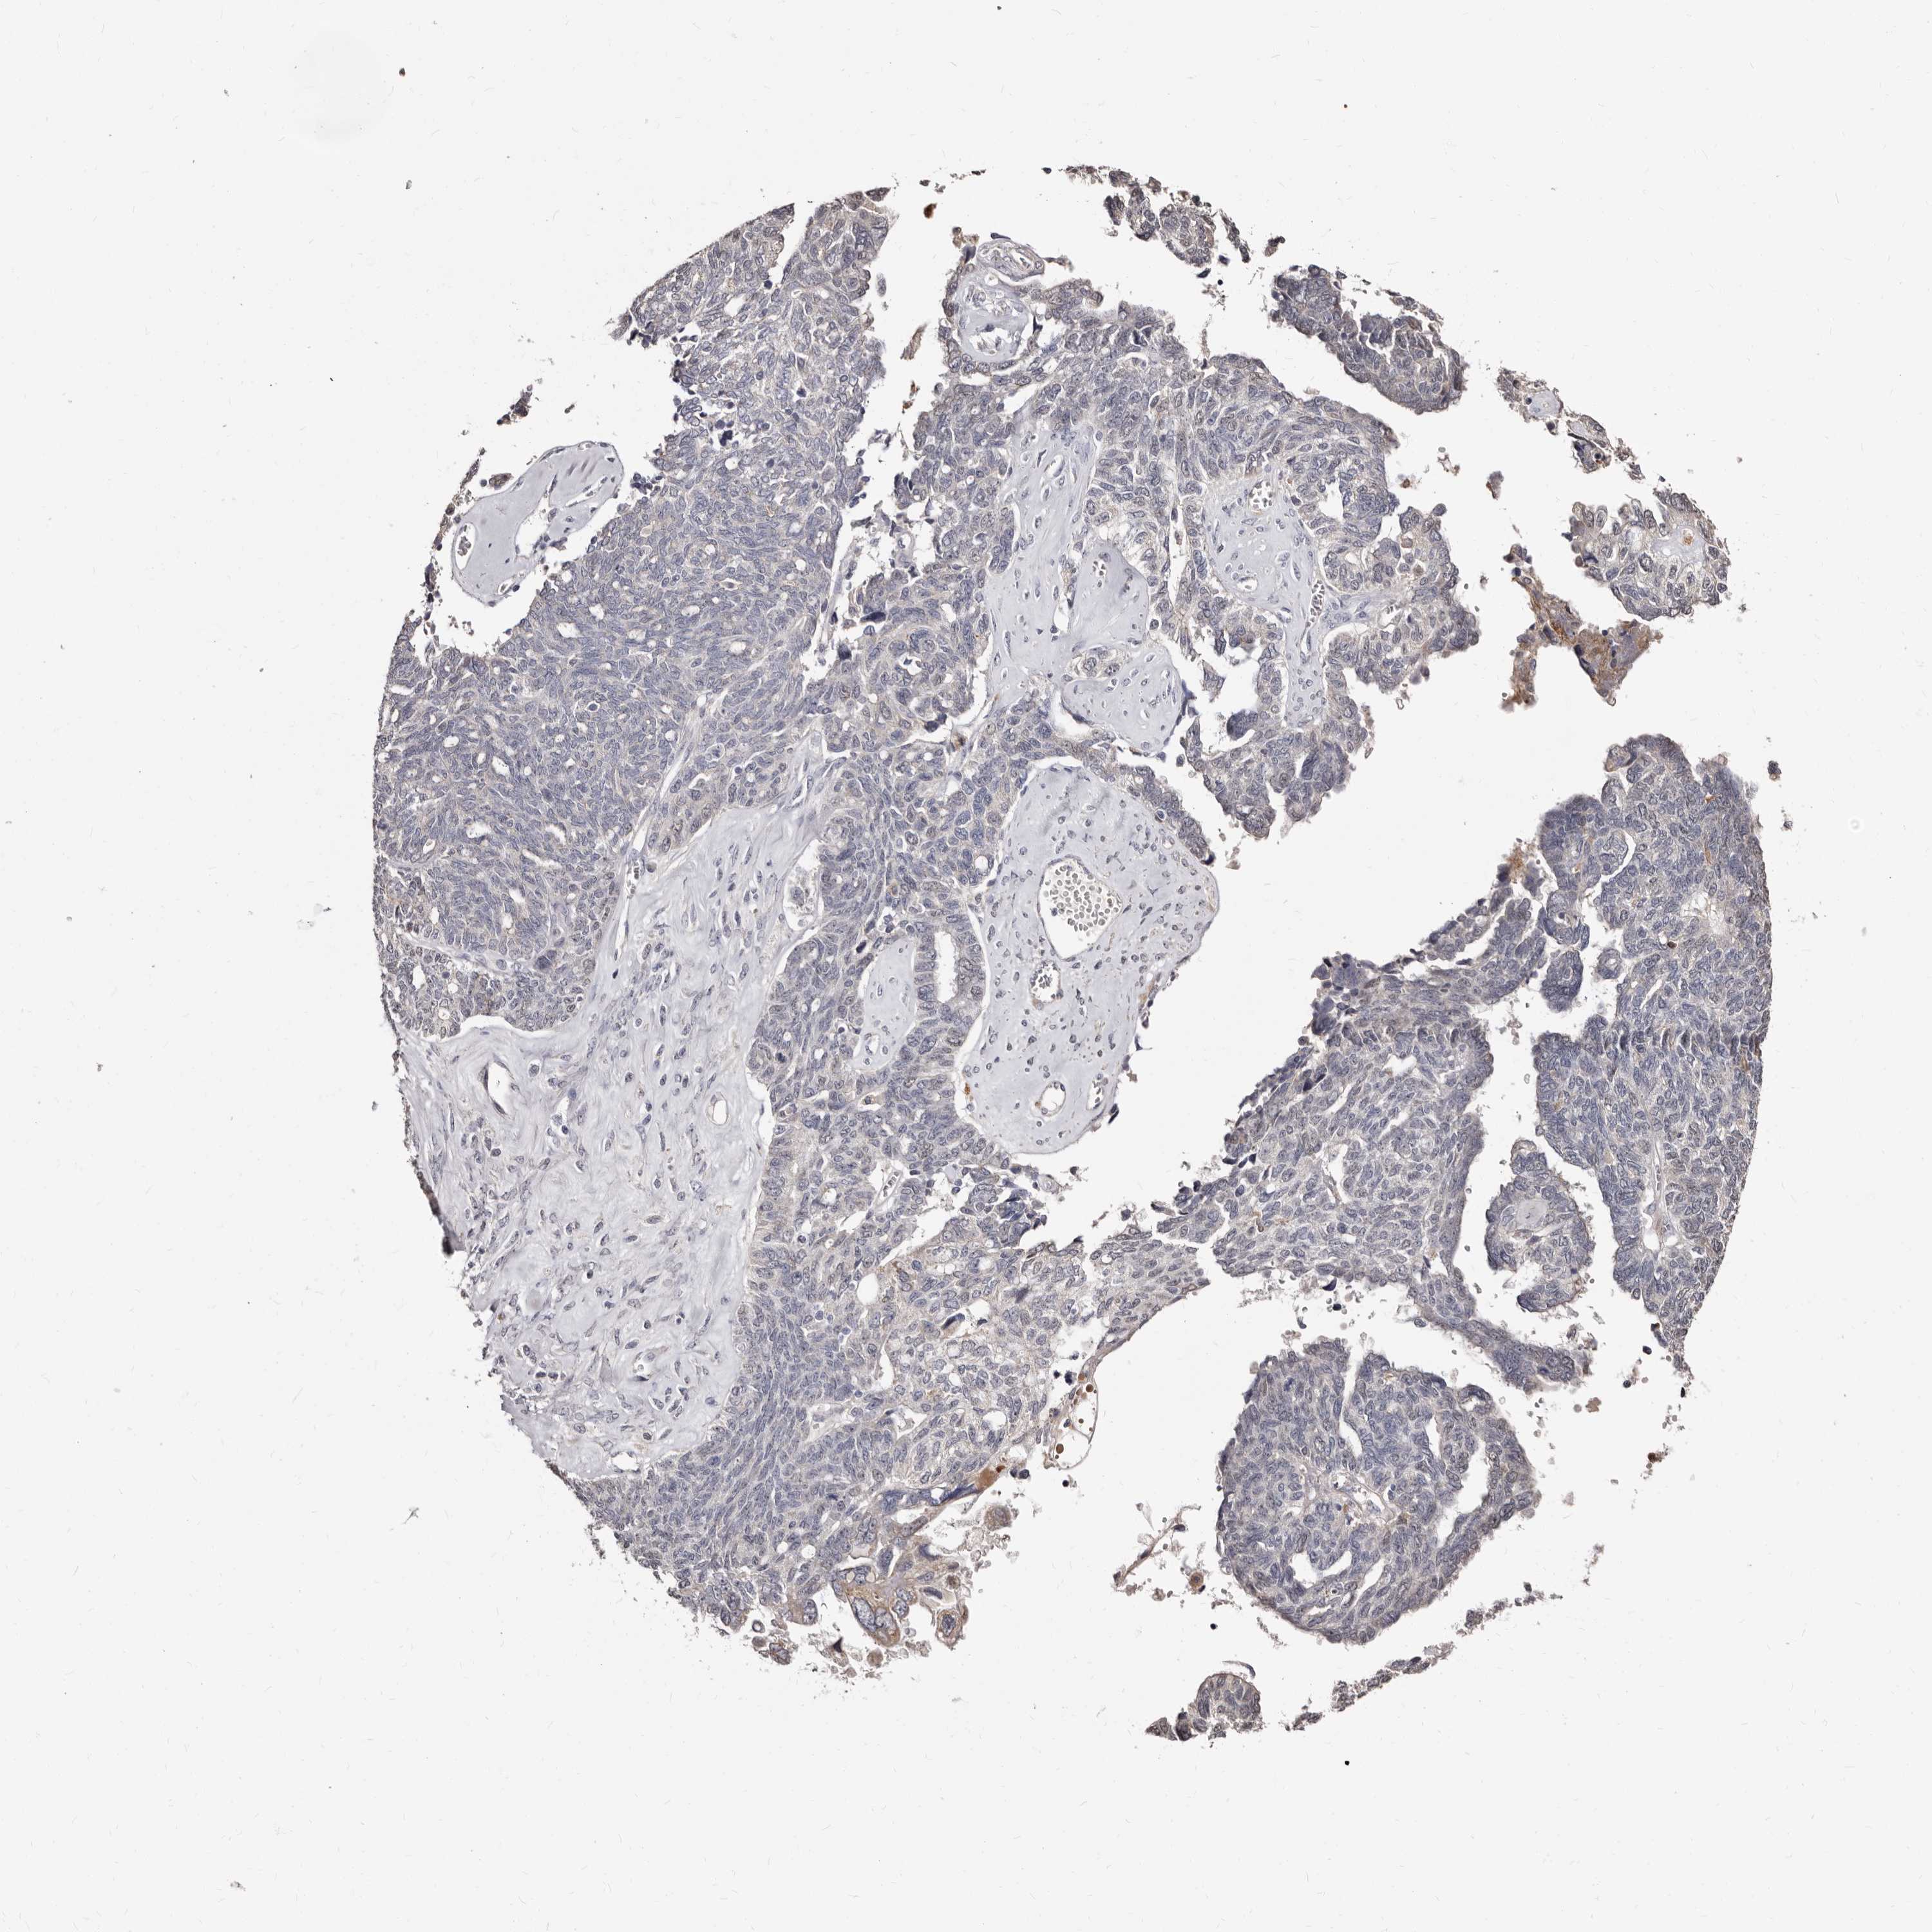

OVARIAN CANCER - Protein expressioni

A mouse-over function shows sample information and annotation data. Click on an image to view it in a full screen mode. Samples can be filtered based on level of antibody staining by selecting one or several of the following categories: high, medium, low and not detected. The assay and annotation is described here.

Note that samples used for immunohistochemistry by the Human Protein Atlas do not correspond to samples in the TCGA dataset.

Antibody stainingi

Antibody staining in the annotated cell types in the current human tissue is reported as not detected, low, medium, or high, based on conventional immunohistochemistry profiling in selected tissues. This score is based on the combination of the staining intensity and fraction of stained cells.

Each image is clickable and will lead to virtual microscopy that enables deeper exploration of all samples and also displays staining intensity scores, fraction scores and subcellular localization as well as patient and tissue information for each sample.

Antibody HPA027543

Staining

High

Medium

Low

Not detected

Intensity

Strong

Moderate

Weak

Negative

Quantity

>75%

75%-25%

<25%

None

Location

Nuclear

Cytoplasmic/membranous

Cytoplasmic/membranous,nuclear

Cystadenocarcinoma, serous, NOS

Carcinoma, endometroid

Cystadenocarcinoma, mucinous, NOS

Carcinoma, NOS